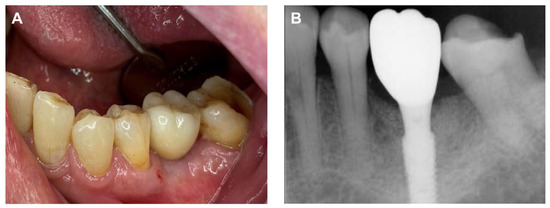

A 78-year-old female patient visited the dental clinic of Daegu Catholic University Medical Center, complaining about a loss of the mandibular left first molar (Figure 1A). The patient had a medical history of hypertension, but she was not taking any medications which needed to be discontinued during the implant procedure. The patient was a non-smoker. For the treatment of choice, it was decided to restore a single implant prosthetic restoration. As a surgical method, flap surgery was planned for bone grafting and implant placement. After the intraoral and radiological examination of the patient, scaling was performed prior to implant placement. The patient received the same pharmacologic protocol of prophylactic oral antibiotics. Amoxicillin sodium (Augmentin; Ilsung pharmaceutical, Seoul, Republic of Korea) with a dosage of 500 mg was to be taken 3 times a day and prescribed routinely, from 1 day before the procedure to 7 days after the procedure. Then, a 4.5 × 10.0 mm implant (AR fixture; Biotem, Seongnam, Republic of Korea) was placed (Figure 1B) with a good initial fixation torque of 40 N/cm2 at placement. After a sufficient healing period of 3 months, the patient received the implant prosthesis.

Figure 1. (A) Pre-operative intraoral periapical radiograph, (B) Post-operative intraoral periapical radiograph.